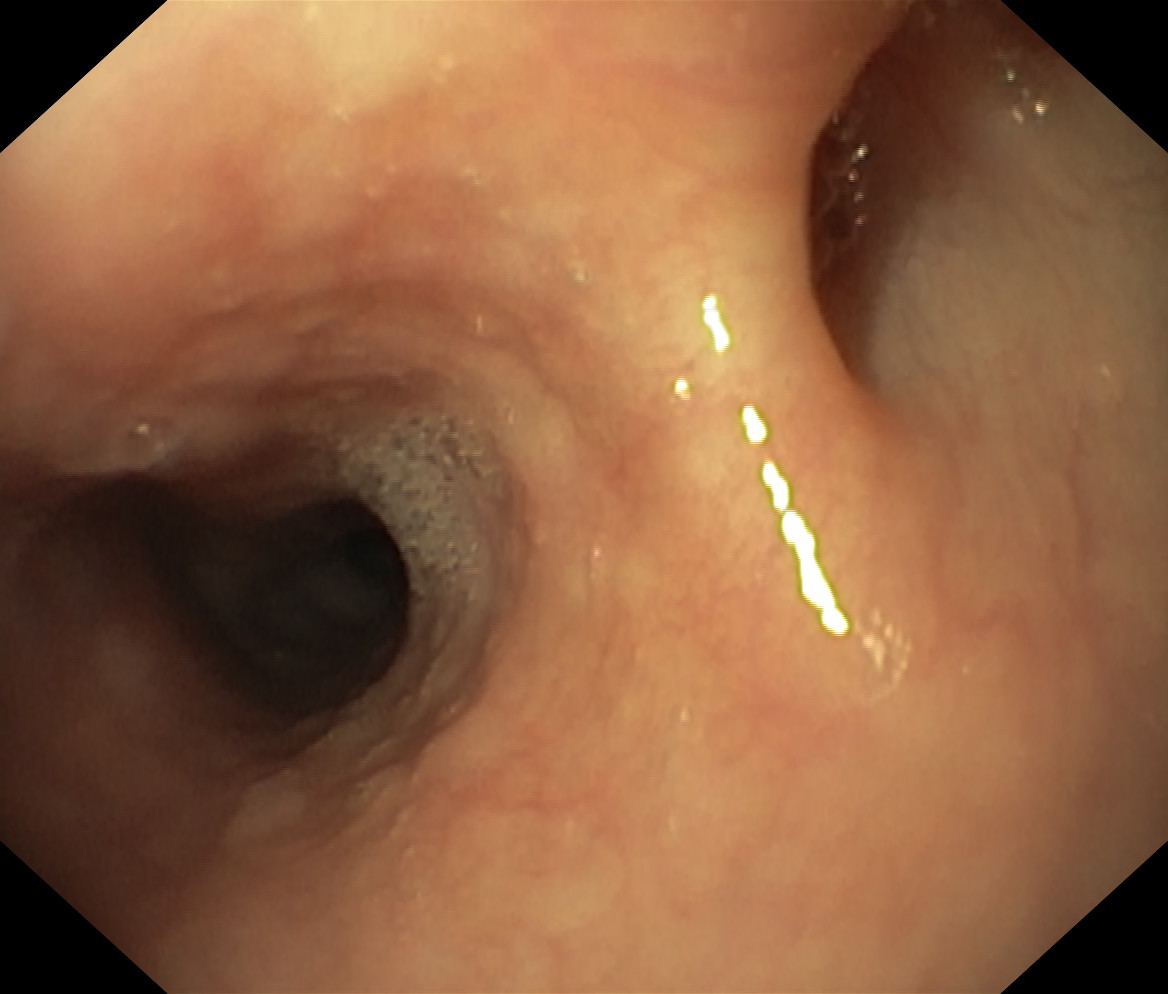

Uchyłki